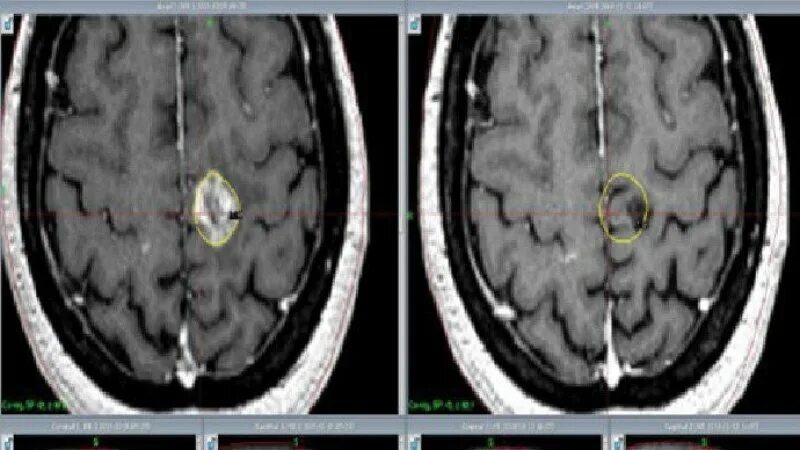

Как умирают от рака головного мозга